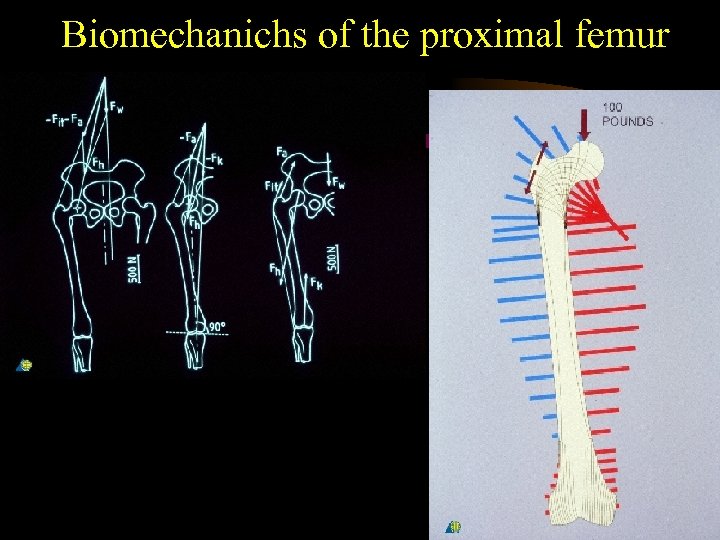

Biomechanichs of the proximal femur

Biomechanichs of the proximal femur

Biomechanichs of the proximal femur

Biomechanichs of the proximal femur

Biomechanichs of the proximal femur

Biomechanichs of the proximal femur